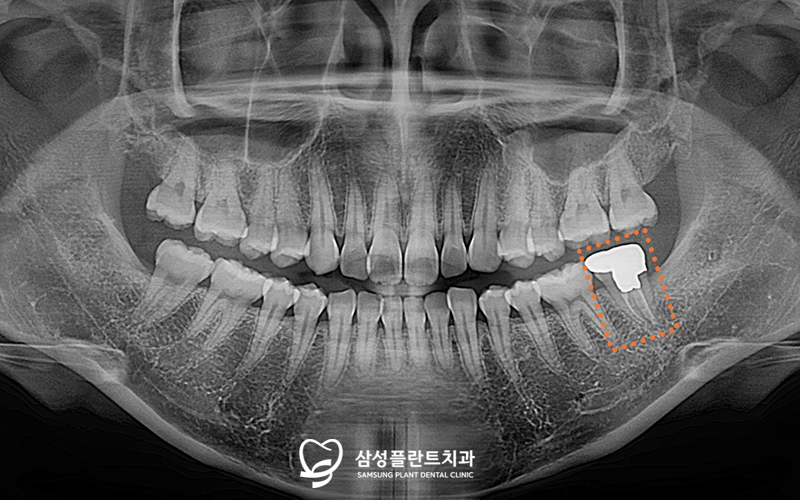

✅ 4개 사랑니 발치 + 인접치 충치치료 완료

신경치료 후에는

어금니가 약해지지 않도록

내부를 단단히 보강한 뒤

크라운(보철물)을 씌워 마무리 해주었답니다.

스케일링과 4개의 사랑니 발치도

깔끔하게 마무리 된

치료 후 모습입니다! 👍

발치 시엔 왼쪽 위아래를 먼저 발치하고

충분히 아물고 나서

오른쪽 위아래를 발치하여

환자분의 불편함을 줄여드렸습니다.